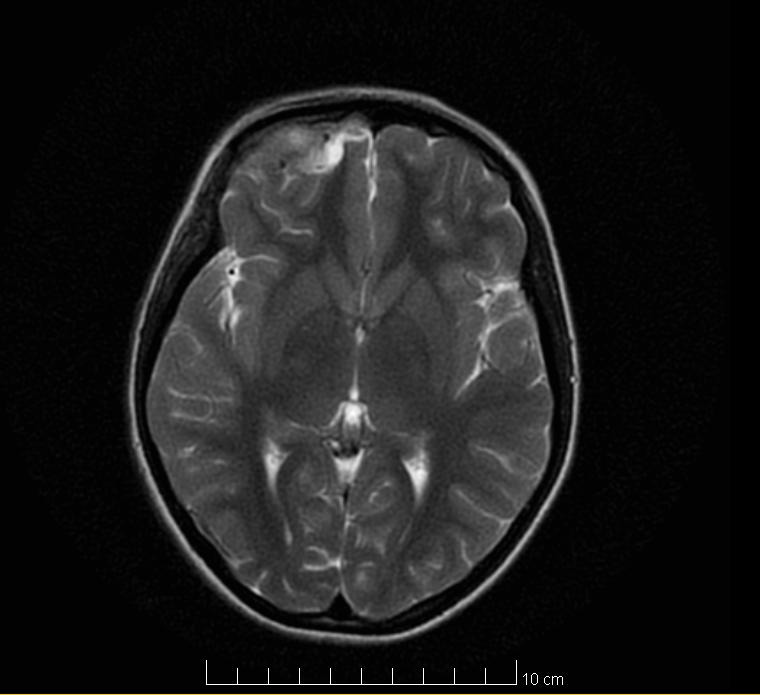

The revaluation imaging tests (brain CT and brain MRI) highlighted the remission of the intracranial purulent collection (Fig. 3), remission of the inflammatory phenomenon on the right orbit, with the recreation of bone structure on the lateral wall of the right ethmoidal lateral mass and the superior wall of the right orbit (Fig. 4).